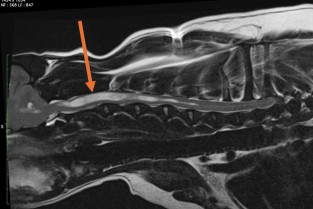

Nous ferons ensuite le point sur le prurit neurogène (syringomyélie, neuropathies sensitives, douleur neurogène et irradiée), sur l’otite et la surdité, mais aussi sur les troubles neurocomportementaux à manifestation cutanée.

- suspecter et d’expliquer une malformation de Chiari ;